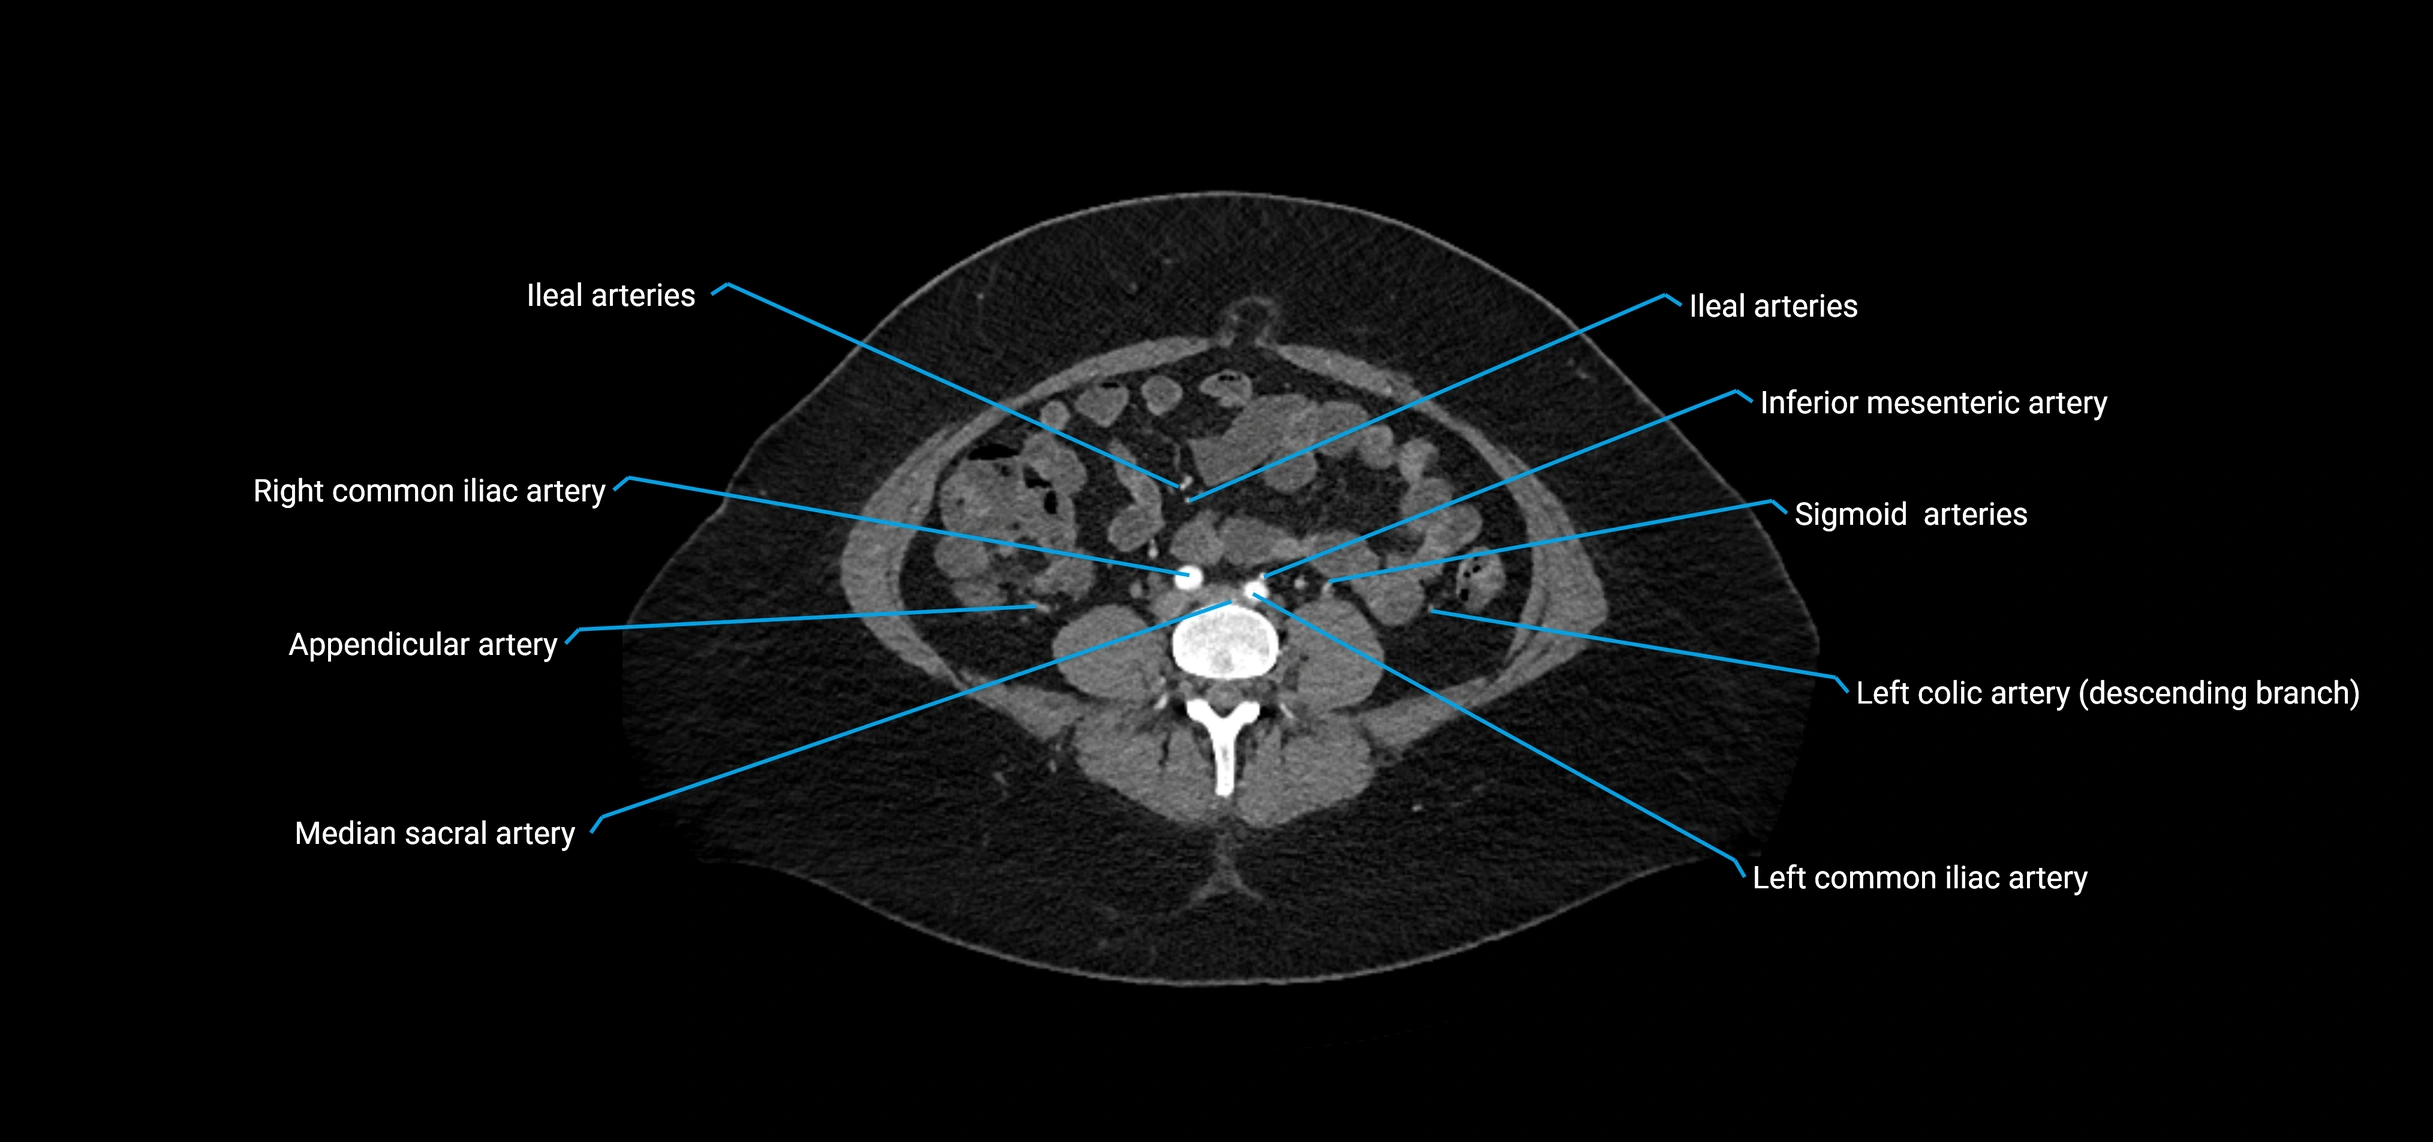

Contrast-enhanced CT (CTA):

• Gold standard for abdominal aortic imaging

• Provides excellent detail of lumen, wall, aneurysm, thrombus, and branch vessels

• Multiplanar and 3D reconstructions help in aneurysm measurement, stent graft planning, and dissection evaluation